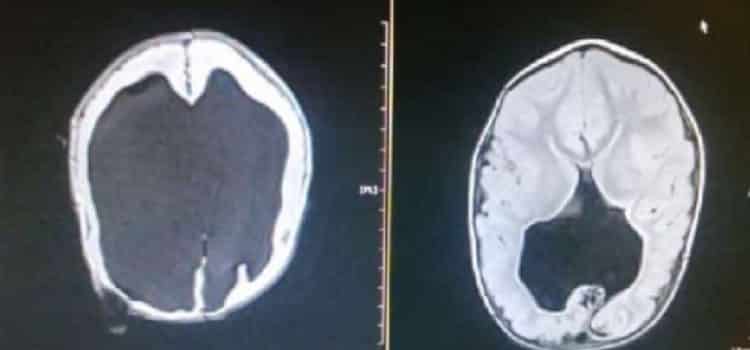

Foi enquanto Shelly Wall ainda estava esperando seu bebê que ela e o marido receberam uma notícia que nenhum pai ou mãe deseja ouvir: as chances de seu filho sobreviver eram mínimas, pois nas ultrassonografias foi constatado que ele era portador de hidrocefalia. Essa condição fazia com que a cabeça do bebê fosse muito grande e, seu cérebro, quase não existisse, havendo apenas 2% de formação.

Depois que o bebê nasceu, mesmo com sua hidrocefalia confirmada e exames apontando que praticamente não havia se formado cérebro, ele foi para casa com seus pais e começou a se desenvolver de forma jamais vista na medicina.

Seu cérebro se desenvolveu quase por completo ao longo desse tempo, graças ao cuidado, amor e incentivo dos seus pais, e claro, um toque da Mãe Natureza. Os médicos não sabem explicar o caso de Noah, por mais que seja destaque em diversos congressos de medicina.